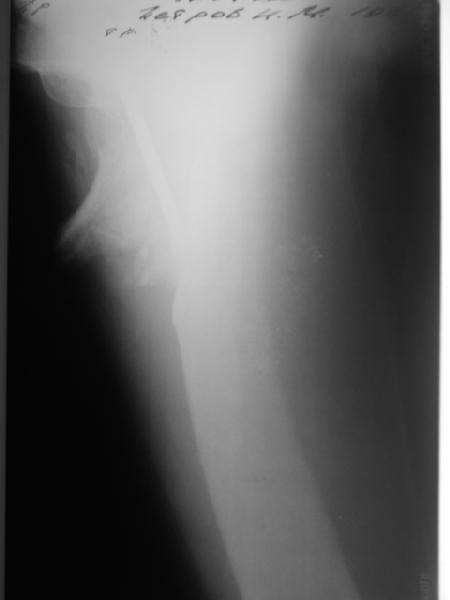

В этом случае, по-моему, аппаратный этап не был уж настолько важен. При использовании DHS или клинковой пластины при таком исходном положении отломков можно было делать и одномоментную коррекцию.

Срубить латеральную стенку периферического отломка для облегчения вальгизации.

В приложении пример пациента, близкого по картине к тому, что представил Виктор (варус и смещение периферического отломка на поперечник кзади). Сделали как раз то, что Виктор исходно намеревался - аппаратная коррекция и затем гамма.